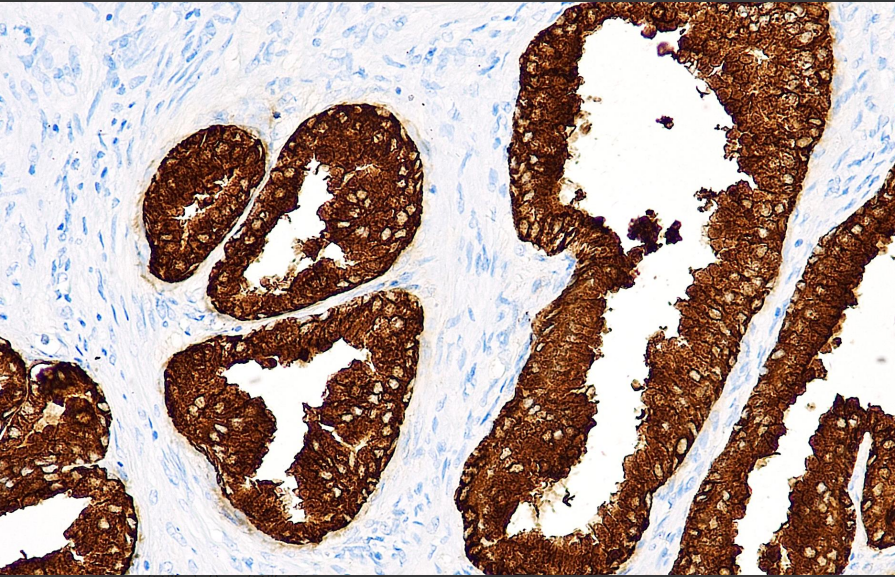

Clone number: OTI1F8

isotype: mouse monoclonal antibody

Cellular localization: cytoplasm

Tissue: paraffin/frozen

Positive control: prostate/prostate cancer

Antibody incubation time: 30-60min

Antigen repair: Thermal repair (EDTA)

PSA antibody reagents can specifically bind to PSA molecular antigens. Immunohistochemistry kits containing PSA antibody reagents are suitable for the auxiliary diagnosis of prostate cancer and metastatic prostate cancer.